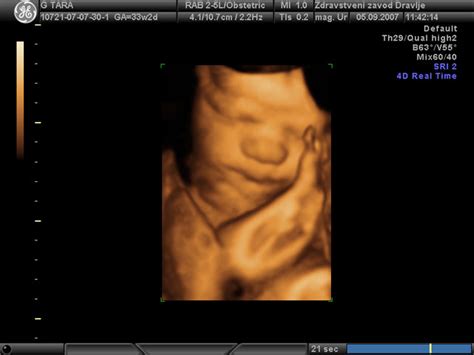

Če do 24. tedna nosečnosti še niste čutili nobenega giba, je to čas, ko se je treba obrniti na zdravstveno stroko. Ginekolog bo preveril srčni utrip ploda, po potrebi pa bo morda potreben tudi ultrazvočni pregled pri specialistu, da se oceni splošna kondicija otroka.